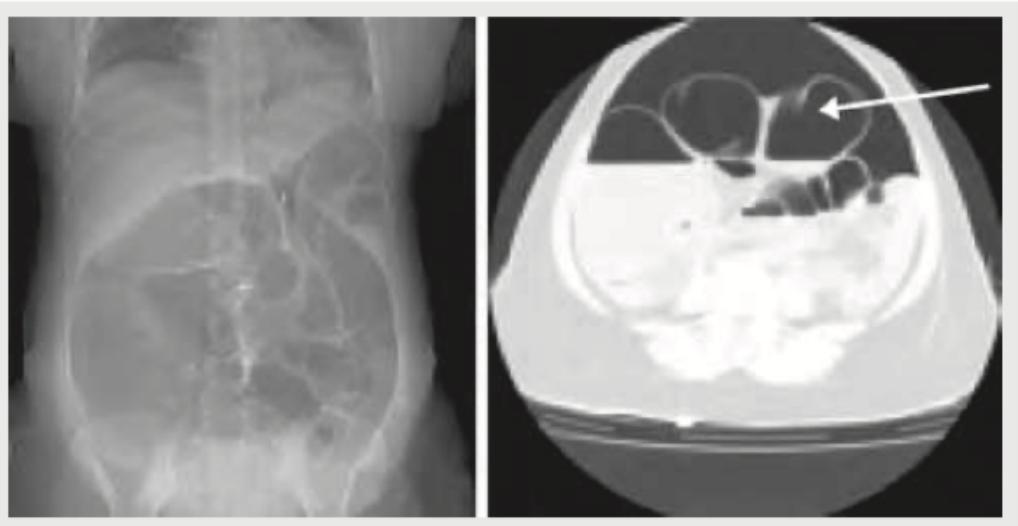

A 30-year-old male presents with acute abdomen. What is the diagnosis based on the CT abdomen given below?

Explanation: ***Rectus sheath hematoma*** - The abdominal X-ray (left image) shows a **large soft tissue mass** in the upper abdomen causing displacement of bowel loops. The CT scan (right image) demonstrates a **well-defined, high-attenuation lesion within the rectus sheath**, indicated by the arrow, consistent with a hematoma. - The appearance of a **fluid collection with high attenuation** on CT in the rectus sheath area, along with the mass effect seen on the plain film, is characteristic of a rectus sheath hematoma. *Small intestinal obstruction* - Small bowel obstruction typically presents with **dilated small bowel loops** and **air-fluid levels** on plain radiographs, which are not the primary finding here. - While there is some bowel gas displacement, the prominent finding is a soft tissue mass rather than classic obstructive patterns. *Large intestinal obstruction* - Large bowel obstruction involves **dilated large bowel loops**, often with **haustral folds**, and may present with a collapsed small bowel distal to the obstruction point. - The images do not show a pattern typical of dilated colon or specific features of large bowel obstruction. *Pneumoperitoneum* - Pneumoperitoneum refers to **free air in the peritoneal cavity**, often visible as air under the diaphragm on an upright chest X-ray or as free air outlining abdominal structures on supine films. - The provided images do not show evidence of free intraperitoneal air; instead, they demonstrate a contained soft tissue mass.